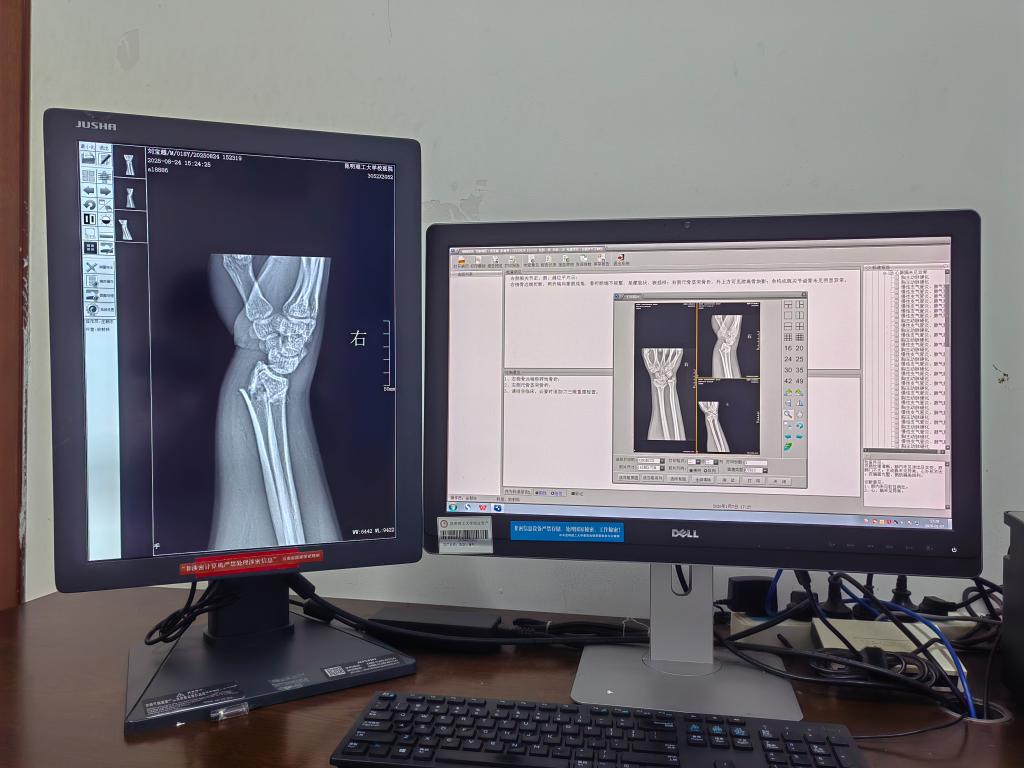

医院配备有X射线数字成像系统(DR)3套,口腔CT机2台,现有专业技术人员4人,包括1名副主任医师、1名放射诊断执业医师、1名主管技师和1名技师。

(一)数字放射摄影(DR)

作为科室基础且高频的检查项目,DR 检查凭借精准、便捷的服务,覆盖多类健康需求:

2.骨及关节 DR:清晰显示骨骼及关节病变,包括骨折、退行性骨关节病、关节炎(如风湿性关节炎、类风湿关节炎等)、骨结核、骨肿瘤等,适用于运动损伤(如扭伤、摔伤、关节疼痛等)、老年骨关节不适等方面的检查;有的同学比较关心自己能否还能长高,可以到医院放射科咨询,检查骨骺线是否闭合。

优势是性价比高:检查速度快、价格亲民(比如每张胸部DR正位检查只需30元),是初步筛查最常用的选择。